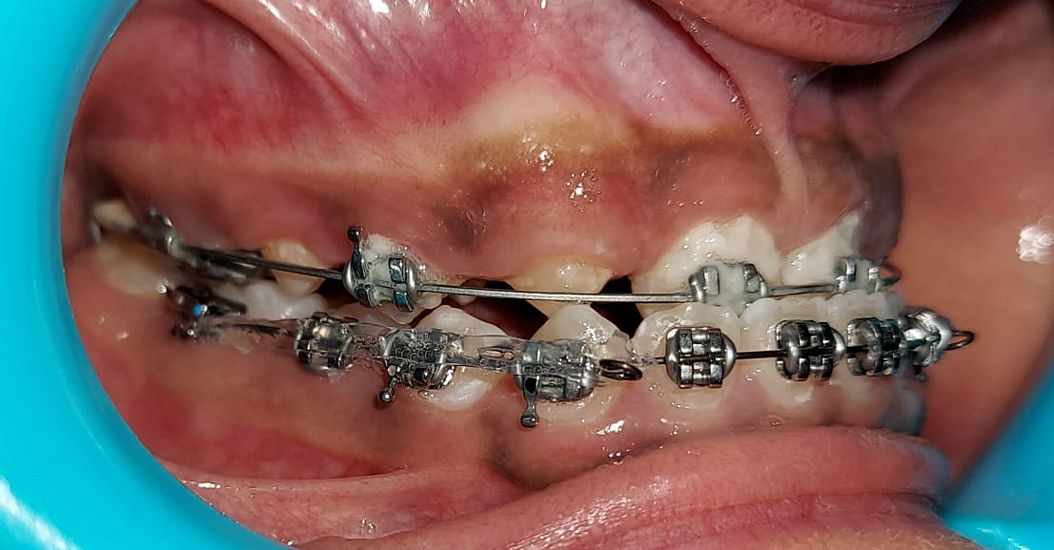

Intra-oral : Mid-treatment : Right Lateral View